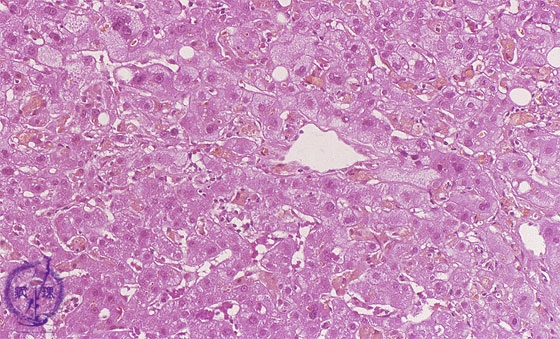

• (10)Cholestatic disease (acute drug-induced)

Microscopic image (HE stain, high power): In addition to centrilobular balloon cell degeneration and multiple scattered bile duct plugs, there are mildly swollen Kupffer cells and focal hepatocellular necrosis.